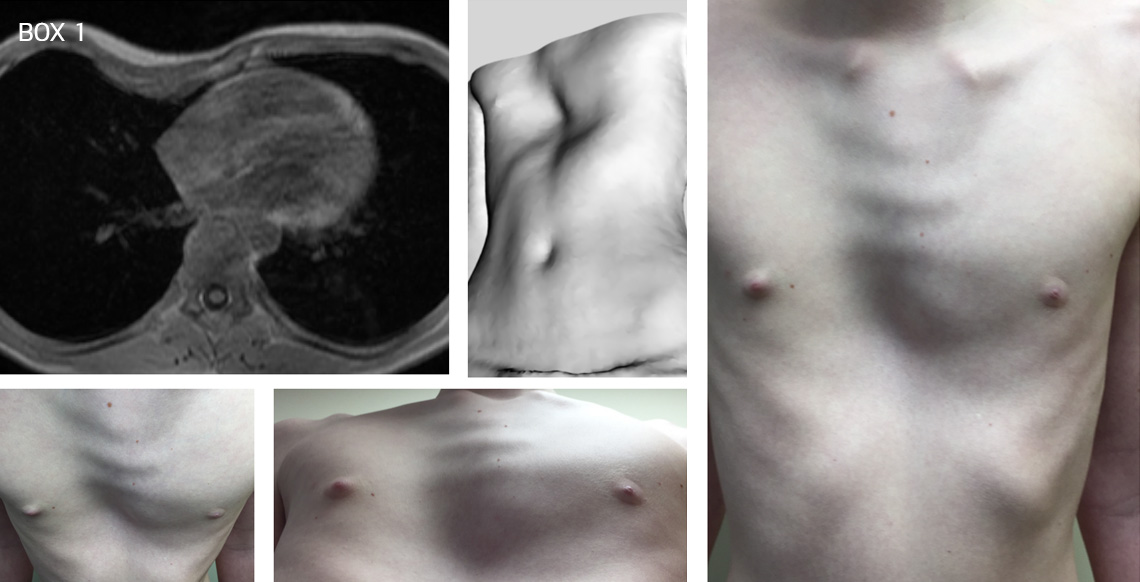

A young boy with a mixed type of pectus deformity with a predominant pectus excavatum and right-sided mild carinatum and associated mild bilateral rib flaring. Before (Box 1) and after a Nuss procedure following bar removal (Box 2)